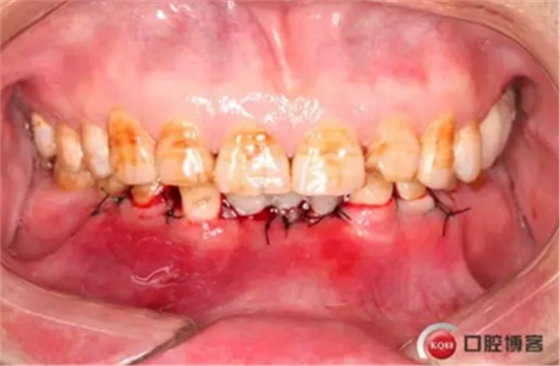

下圖是術(shù)后照片 治療過程 術(shù)前測(cè)量上下牙長(zhǎng)度比例,確定水激光冠延長(zhǎng)深度約3mm,拔除31、41,在術(shù)區(qū)減低牙槽嵴高度,32、42位點(diǎn)種植MINI型一段式種植體,使用臨時(shí)愈合帽行暫時(shí)性修復(fù)。

治療前后照片顯示患者上下臨床牙冠比例協(xié)調(diào),患者對(duì)臨時(shí)修復(fù)體效果十分滿意。當(dāng)然有待后期愈合及長(zhǎng)期的臨床隨訪,以觀察遠(yuǎn)期臨床效果。將水激光應(yīng)用臨床冠延長(zhǎng),有利于精準(zhǔn)去除骨量,利于術(shù)后愈合。而MINI型一段式種植體滿足骨寬度不足,及臨時(shí)修復(fù)打下堅(jiān)實(shí)基礎(chǔ)。